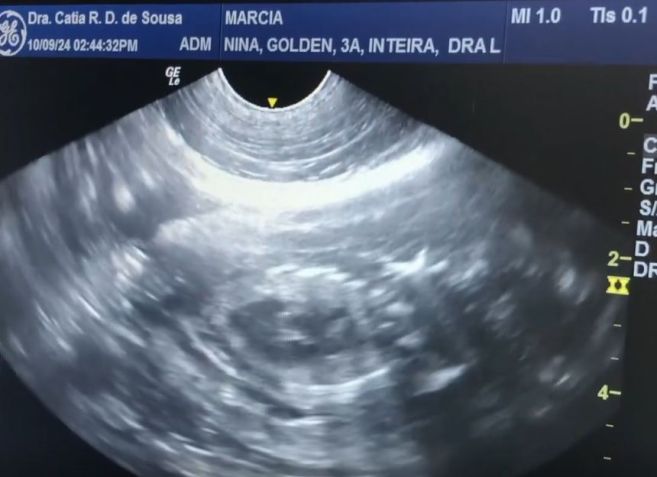

Nas redes sociais, Márcia conta que após um parto trabalhoso, Nina deu vida a nove filhotes, sendo seis machos e três fêmeas. A chegada ao mundo, no entanto, foi graças à cesariana necessária, em virtude da ausência no trabalho de parto da cachorra.